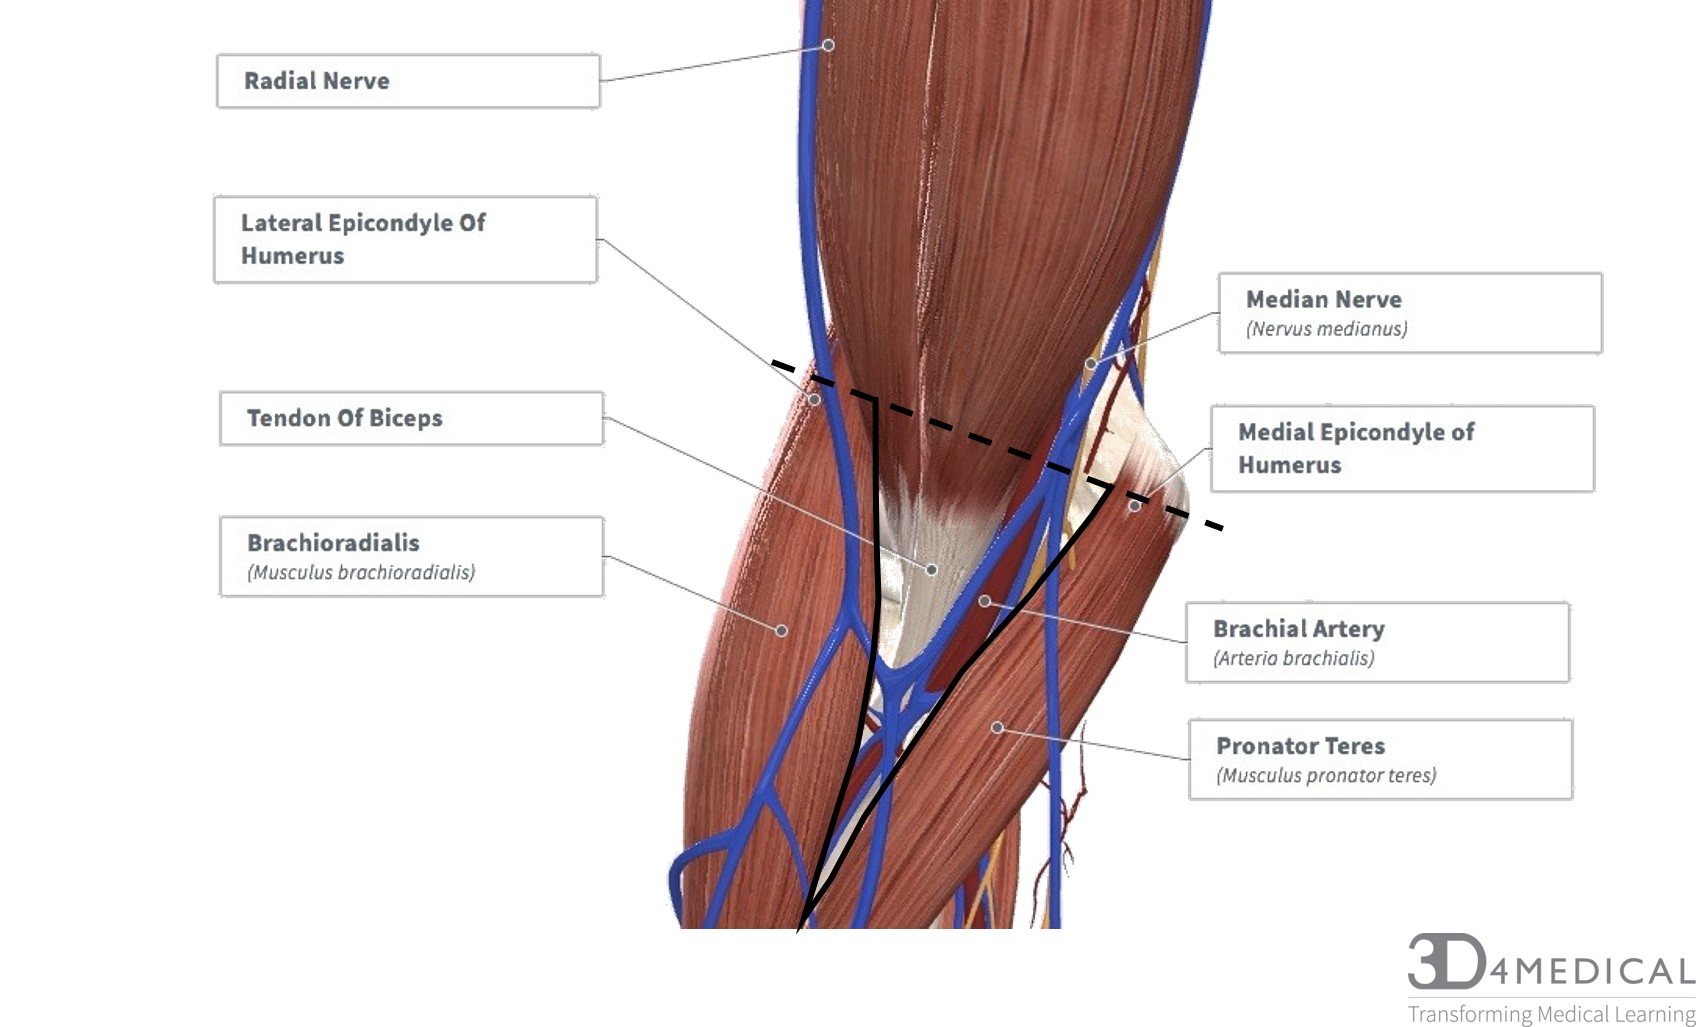

Анатомия и функции мышцы brachioradialis